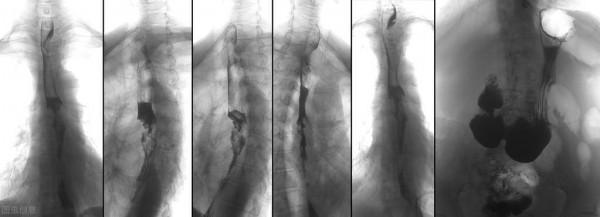

醫院給徐先生儘快安排了手術,術後病理提示為鱗癌,腫瘤侵及肌層,未見區域淋巴結轉移,最終診斷為食管鱗癌Ⅱa期,做完手術也沒給徐先生安排放化療